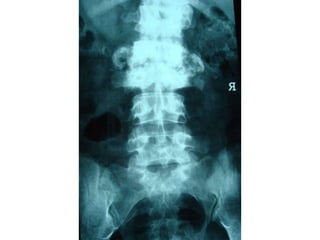

charcot joint

charcot joint by dr khaled abdelbaky